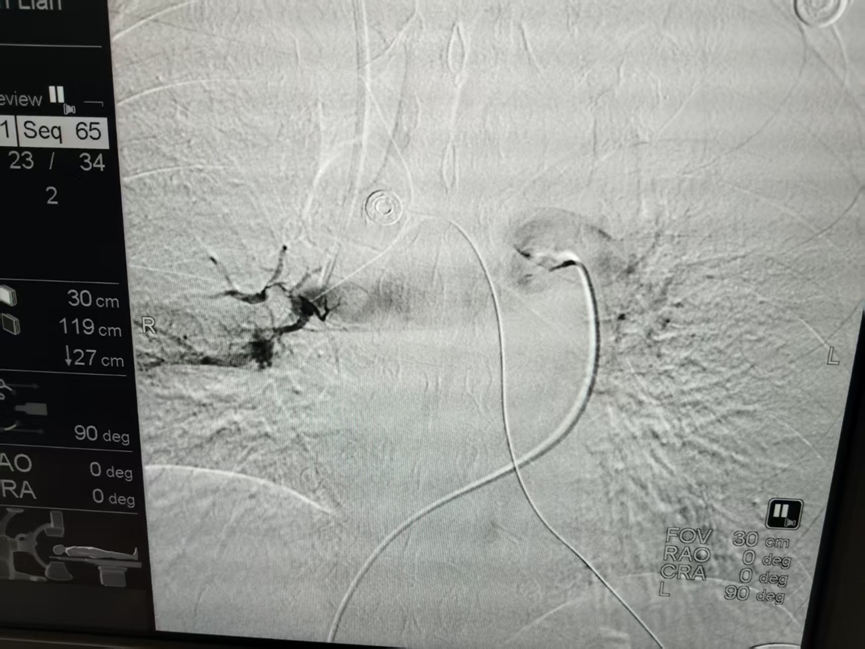

术前造影

给予普通PTA球囊扩张导管(5.0和6.0)扩张肺动脉主干及二级血管,更换加硬导丝后置入Tendvia®肺动脉取栓支架,在预定位置(左肺动脉二级下段血管)打开支架后拉出血凝块约20ml。造影未见明显造影剂外渗。

取栓中

术后造影